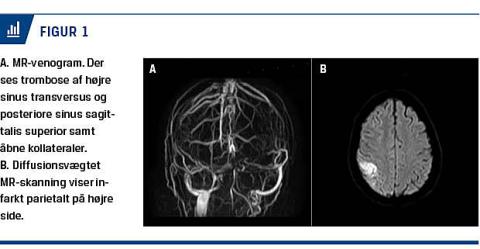

af empyemet, men dette kunne ikke påvises ved MR-skanning. Symptomerne blev tolket som meningeal irritation. Dagen efter indtrådte der igen forværring med generaliserede krampeanfald. En CT viste sløring af mellemøre og mastoid trods dræn. Der blev udført mastoidektomi. En MR-skanning med venogram viste trombose af højre sinus transversus og posteriore sinus sagittalis superior (Figur 1A) samt tegn på venøst infarkt på højre side (Figur 1B). Der blev påbegyndt antikoagulans (AK)-behandling. Ud over en p-stav, som blev fjernet, havde patienten ingen kendte trombogene risikofaktorer. Efter fire uger blev hun udskrevet til kortvarig rehabilitering pga. milde kognitive deficit.

En MR-skanning efter fire måneder viste rekanalisering af tromben og regression af infarktet, og AK-behandlingen blev seponeret. Der var ingen tegn på lungeemboli.